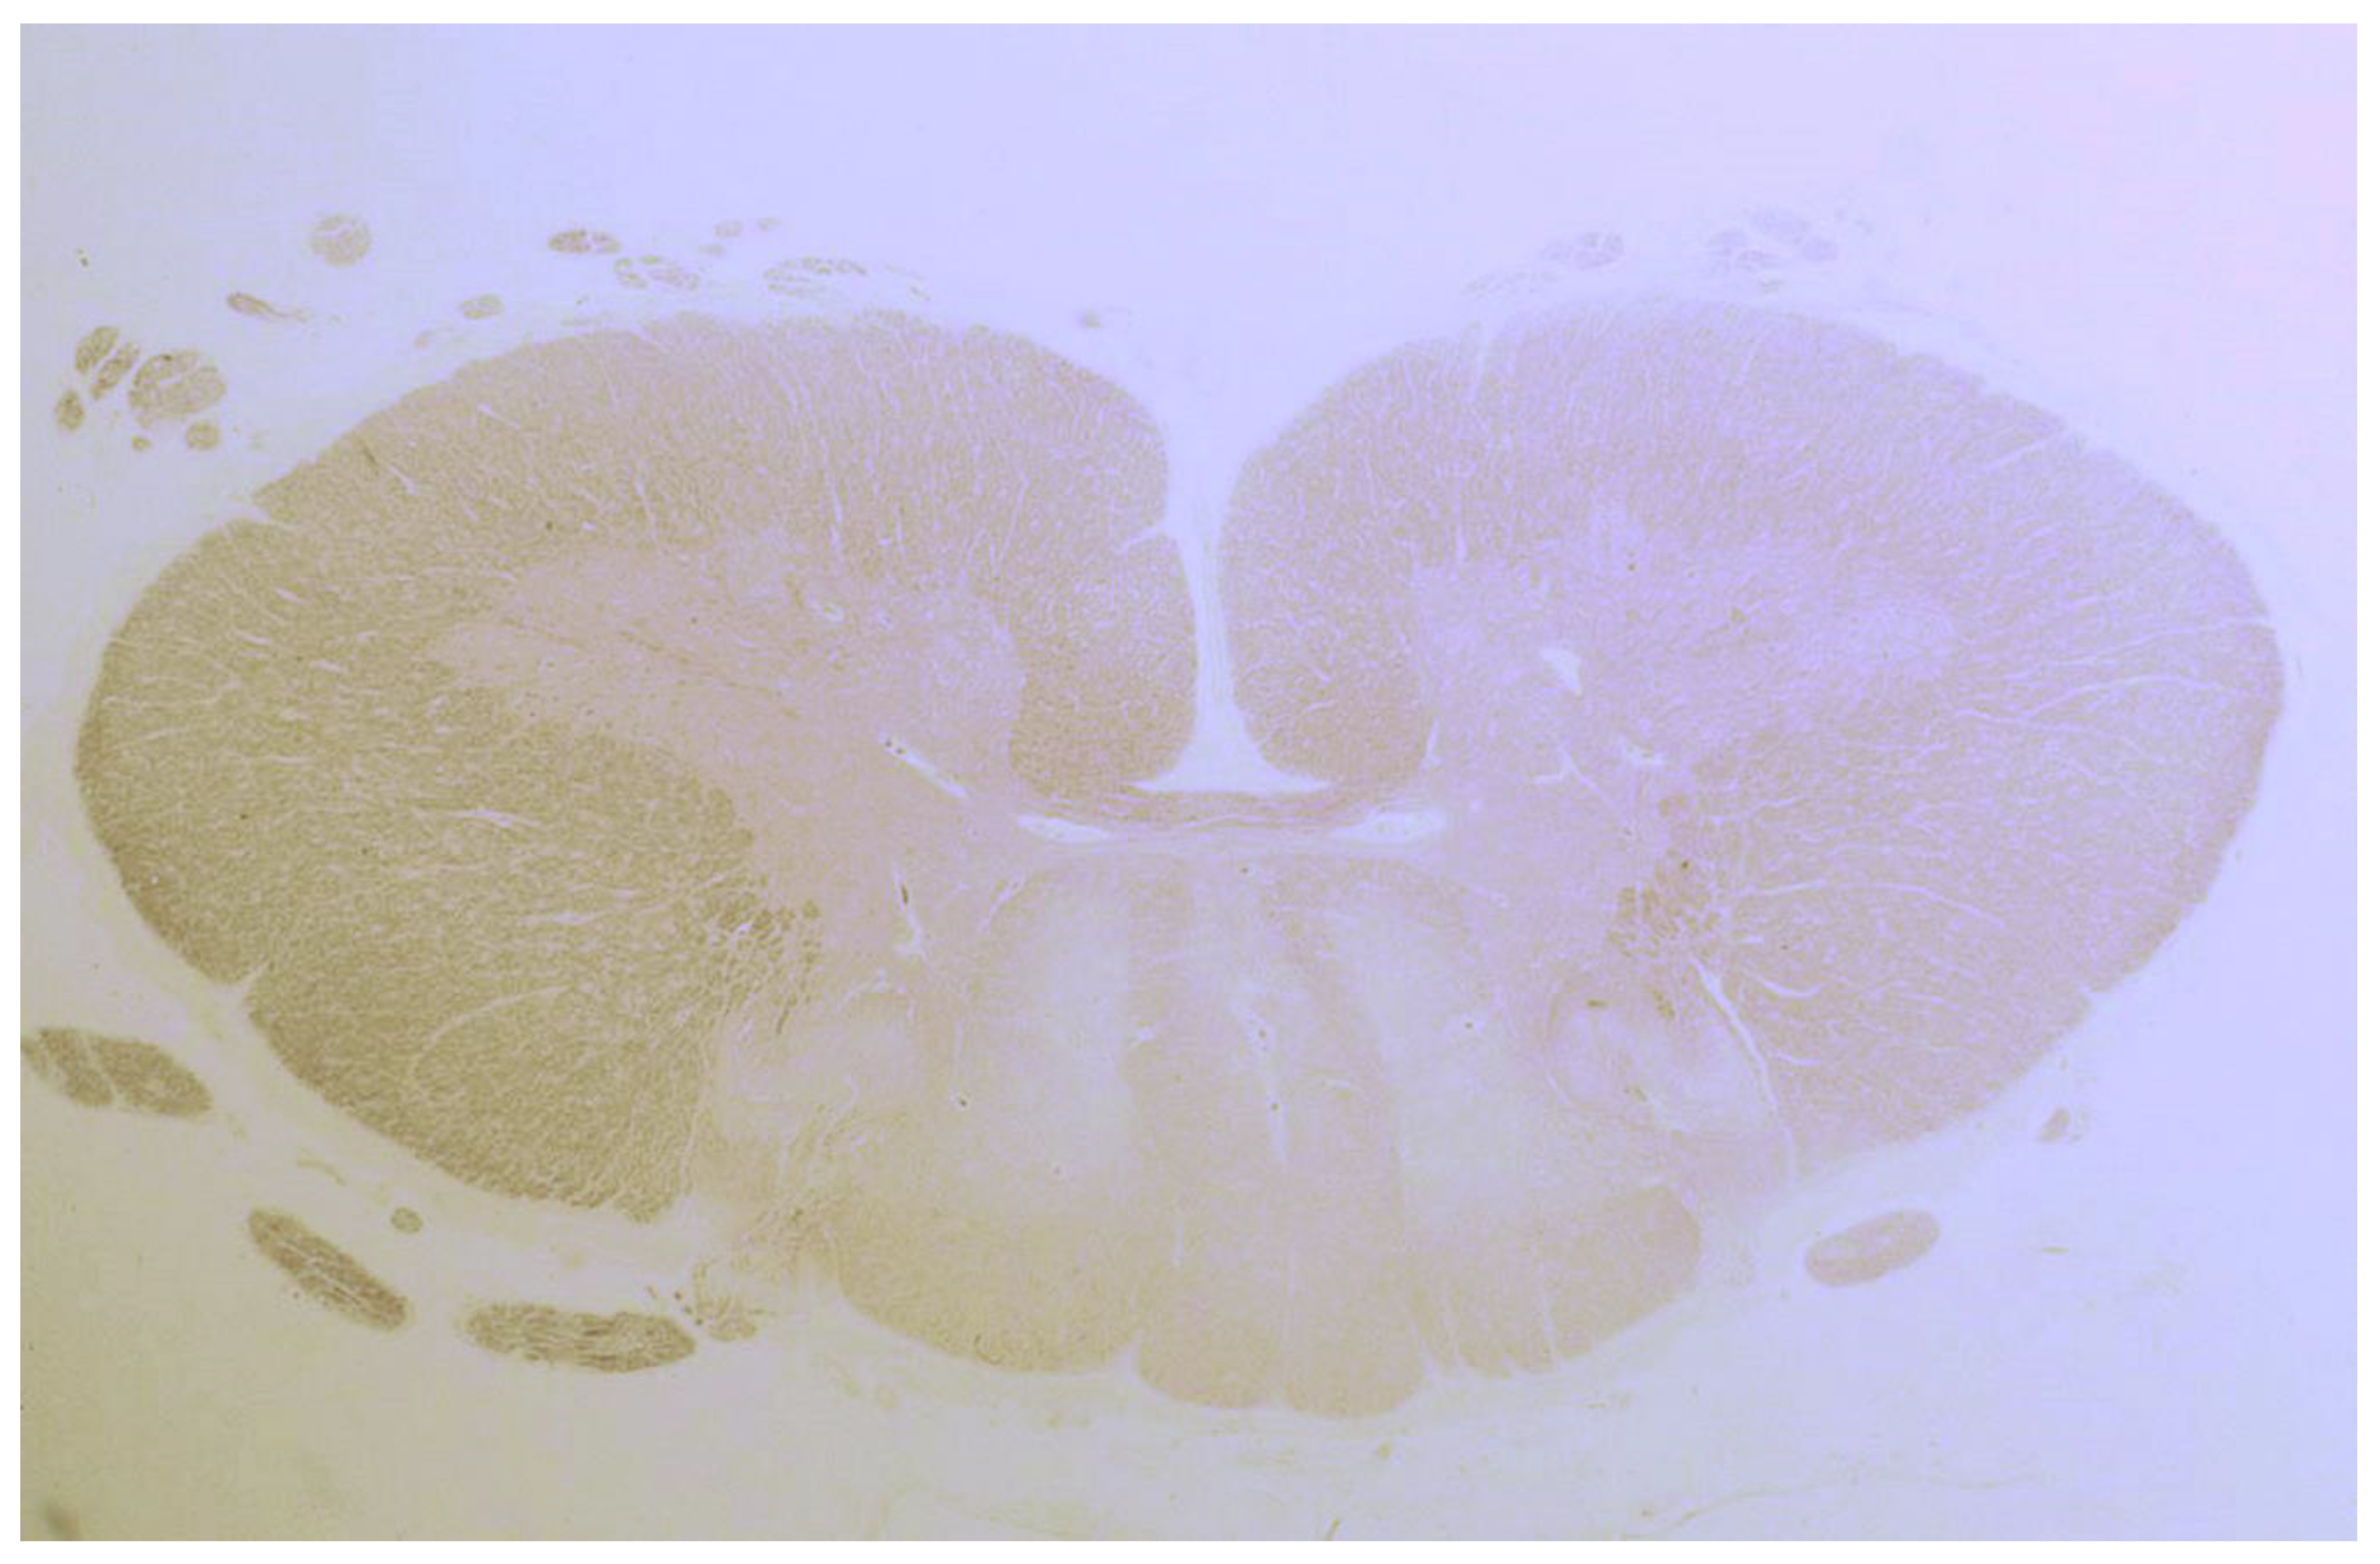

| Cooke 1966, UK (I) * | 9 | Brain Spinal cord | Loss of Purkinje cells; atrophy and gliosis of the dentate nucleus, cerebrum, inferior olives, thalamus and hypothalamus; demyelination of post. & ant.-lat. columns; focal perivascular lymphocytic cuffing, chromatolysis and sudanophil lipophages throughout the CNS. |

| Finelli 1980, USA | 1 | Brain Spinal cord | Loss of Purkinje and granular layer cells; Neuronal loss & gliosis basal ganglia, inferior olives, substantia nigra; Demyelination ant. & lat. corticospinal tracts |

| Kinney 1982, USA | 1 | Brain | Loss of Purkinje cells; atrophy, gliosis of the dentate nucleus, cerebellar granular layer, thalamus, hypothalamus & periaqueductal grey; Senile plaques in the neocortex & hippocampi; Cerebral gliosis subcortical & white matter |

| Mittelbronn 2010, Germany | 1 | Brain | Loss of Purkinje cells & cerebellar granular layer cells; Cerebellar atrophy and astrocytic gliosis; Severe neuronal loss inferior olives & accumulation of corpora amylacea. Cerebral reactive astrogliosis and microglial activation Inflammation dominated by CD8+/granzyme B+ & CD20-/CD138- diffuse infiltrates & perivascular cuffing in the cerebellum and brainstem |